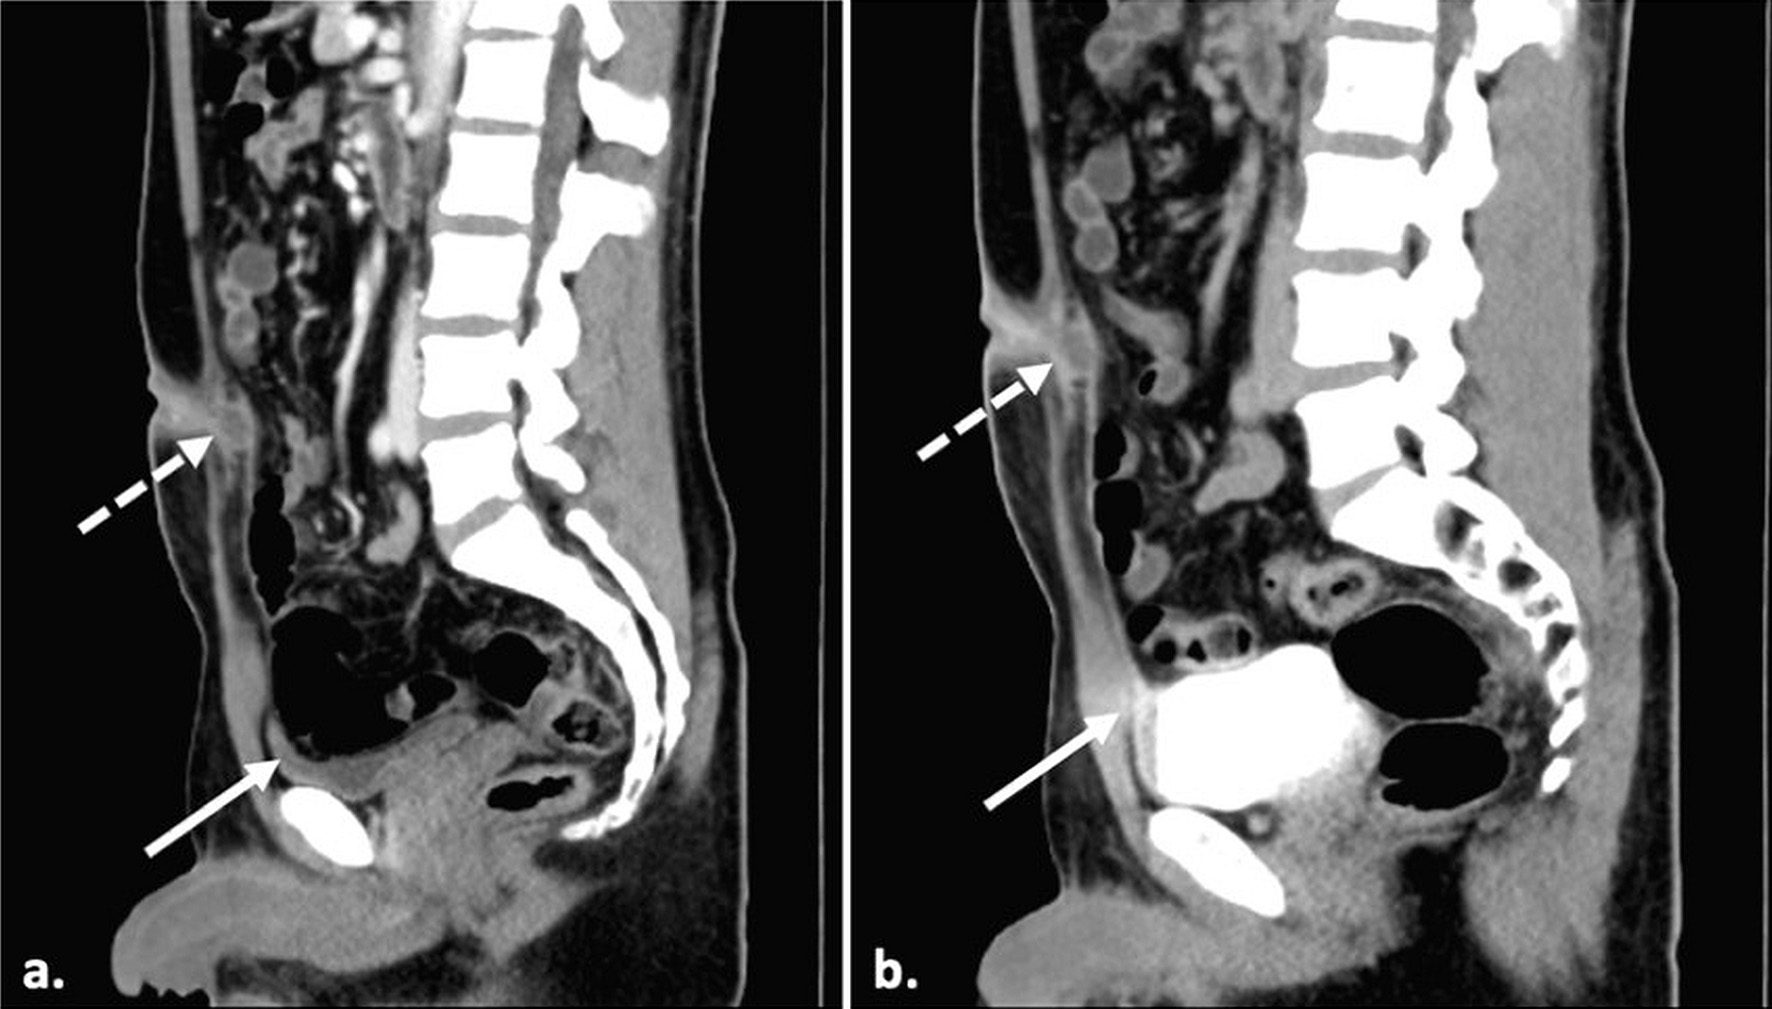

Laboratory investigations showed a normal white blood cell (WBC) count of 10 × 109/L and an elevated C-reactive protein (CRP) level of 5.6 mg/L. Renal and liver function tests were within normal parameters. The fasting plasma glucose was also within the normal range (5 mmol/L). During this consultation at the primary care clinic, a provisional diagnosis was an umbilical abscess, and the patient was referred for inpatient management, including intravenous antibiotics, imaging, and surgical evaluation. In the hospital, abdominal ultrasonography revealed an irregular hypoechoic collection within the rectus muscle and continuous with the subcutaneous tissue at the umbilical region, measuring approximately 2.2 × 2.7 × 1.9 cm. No intraperitoneal extension was demonstrated. Subsequent contrast-enhanced computed tomography (CT) of the abdomen and pelvis demonstrated a rim-enhancing fluid collection at the umbilicus measuring 2.1 × 1.7 × 1.7 cm, consistent with an infected umbilical urachal sinus (Fig. 2). Surrounding fat stranding was observed, indicative of localized inflammation. Additionally, the CT scan identified a vesicourachal diverticulum (Fig. 3a, b), characterized by a tubular tract extending from the anterior dome of the bladder towards the umbilicus.

Click for large image

Figure 3. Midsagittal CT scan images of (a) contrast-enhanced scan and (b) delayed images with a full bladder showing the partially filled vesicourachal diverticulum (solid arrow) and the infected umbilical-urachal sinus (dashed arrow). There is no evidence of communication of the umbilical-urachal sinus with the bladder lumen.

When a urachal anomaly is suspected, Yiee et al recommend ultrasonography as the initial imaging modality due to its high sensitivity in detecting various types of urachal anomalies [12]. A urachal sinus typically appears on ultrasound as a tubular, hypoechoic structure that communicates exclusively with the umbilicus [17]. While ultrasonography serves as an accessible first-line modality for primary care providers, CT can be valuable in confirming or clarifying uncertain findings, particularly in the context of an infected umbilical urachal sinus. When ultrasound fails to yield a definitive diagnosis or when no umbilical drainage is observed, CT should be considered the next imaging step. CT imaging can help differentiate between a urachal cyst and other intra-abdominal pathologies, such as appendicitis or Meckel’s diverticulitis [12]. A CT scan will usually demonstrate a thickened and fusiform dilation of the urachus at the umbilical end, with no connection to the bladder [8]. In this case, both ultrasound and CT imaging were pivotal in establishing the diagnosis of an infected umbilical urachal sinus.